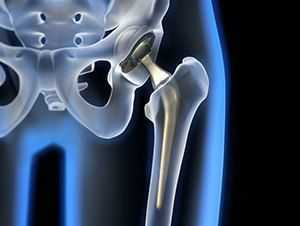

Тазобедренный сустав является сложным многоосным сочленением, которое выполняет сгибание/разгибание, отведение/приведение, пронацию и супинацию бёдер и принимает на себя серьёзную нагрузку. Любые нарушения в его функционировании не только приводят к серьёзному дискомфорту для человека, но и могут стать причиной развития серьёзных нарушений. Рентген тазобедренного сустава (ТБС) — это неинвазивный диагностический метод, ценность которого сложно переоценить.

Он нашёл широкое применение в разных областях медицины, включая травматологию, ревматологию, ортопедию, гнойную хирургию для диагностики заболеваний и последствий перенесённых травм, для определения объёма предстоящей операции или эффективности проведённого лечения. Процедура достаточно безопасна, высокоэффективна и проста, но при этом позволяет получить ценные данные о состоянии ТБС пациента.

Помимо этого, рентгенография таза и тазобедренных суставов проводится в рамках предоперационной подготовки с целью определить объём вмешательства и его тактику.